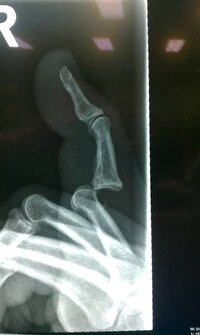

Blade said:I have this really cool stainless steel pin in my finger. It is supposed to hold it all together but it is really uncomfortable. It has been in almost a week and I fear it has to be in allot longer.

I have already missed a 3 day golf trip with my friends and who knows what else in the next while.

xtitan1 said:Injuries can mess with your head a lot more than people realize. Keep strong and keep positive man. It sucks that you missed out on a trip but it could have been a whole heck of a lot worse so you have a lot to be thankful about not upset about. Eventually your finger will heal and if you follow the doctors orders and do your physical therapy you will be good as new before you know it. Even though there was no reason to think otherwise I remember thinking there was no way I would ever be the same again, but I was wrong! Just keep the end picture in sight man!